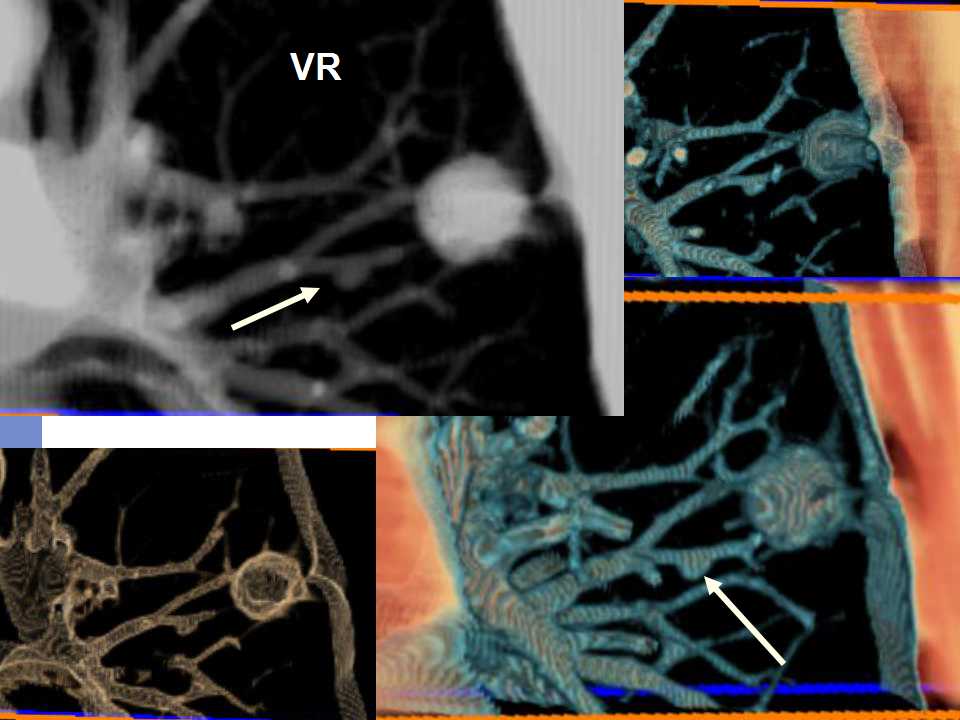

肺癌影像诊断